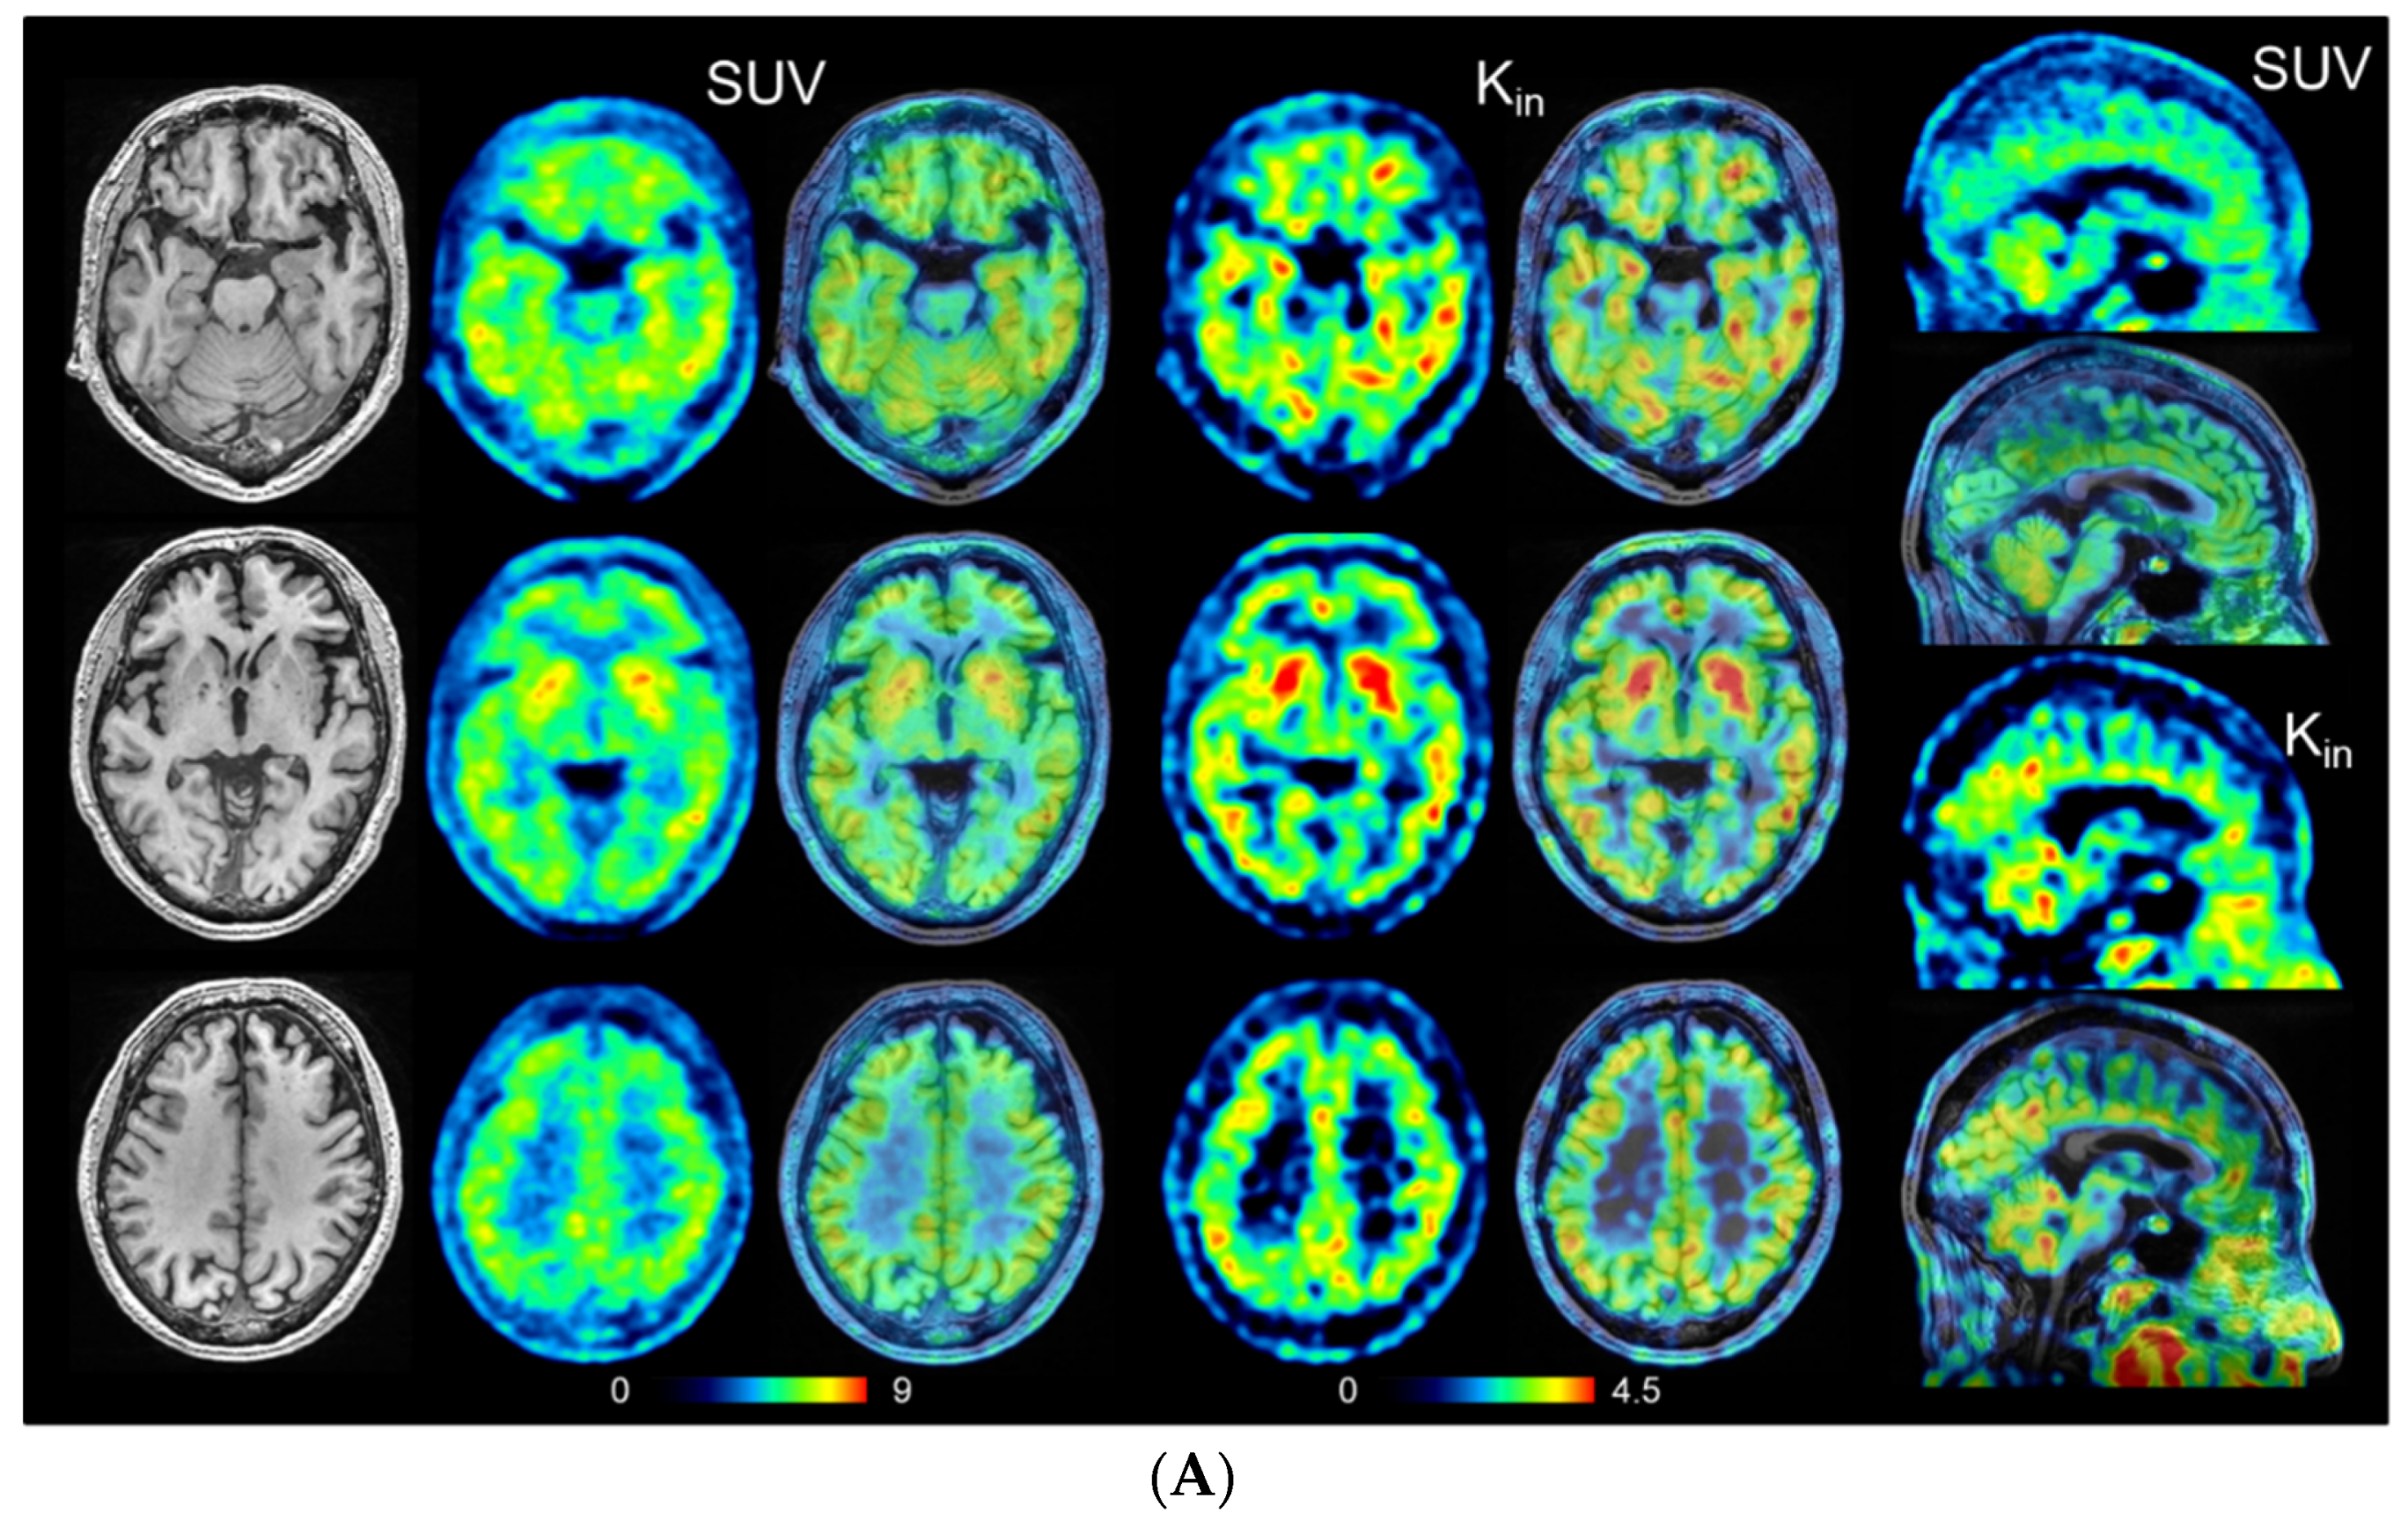

2.3. Calculation of Parametric Images

- Okazawa, H.; Ikawa, M.; Jung, M.; Maruyama, R.; Tsujikawa, T.; Mori, T.; Rahman, M.G.M.; Makino, A.; Kiyono, Y.; Kosaka, H. Multimodal analysis using [11C]PiB-PET/MRI for functional evaluation of patients with Alzheimer’s disease. EJNMMI Res. 2020, 10, 30. [Google Scholar] [CrossRef]

- Okazawa, H.; Ikawa, M.; Tsujikawa, T.; Makino, A.; Mori, T.; Kiyono, Y.; Kosaka, H. Noninvasive measurement of [11C]PiB distribution volume using integrated PET/MRI. Diagnostics 2020, 10, 993. [Google Scholar] [CrossRef] [PubMed]